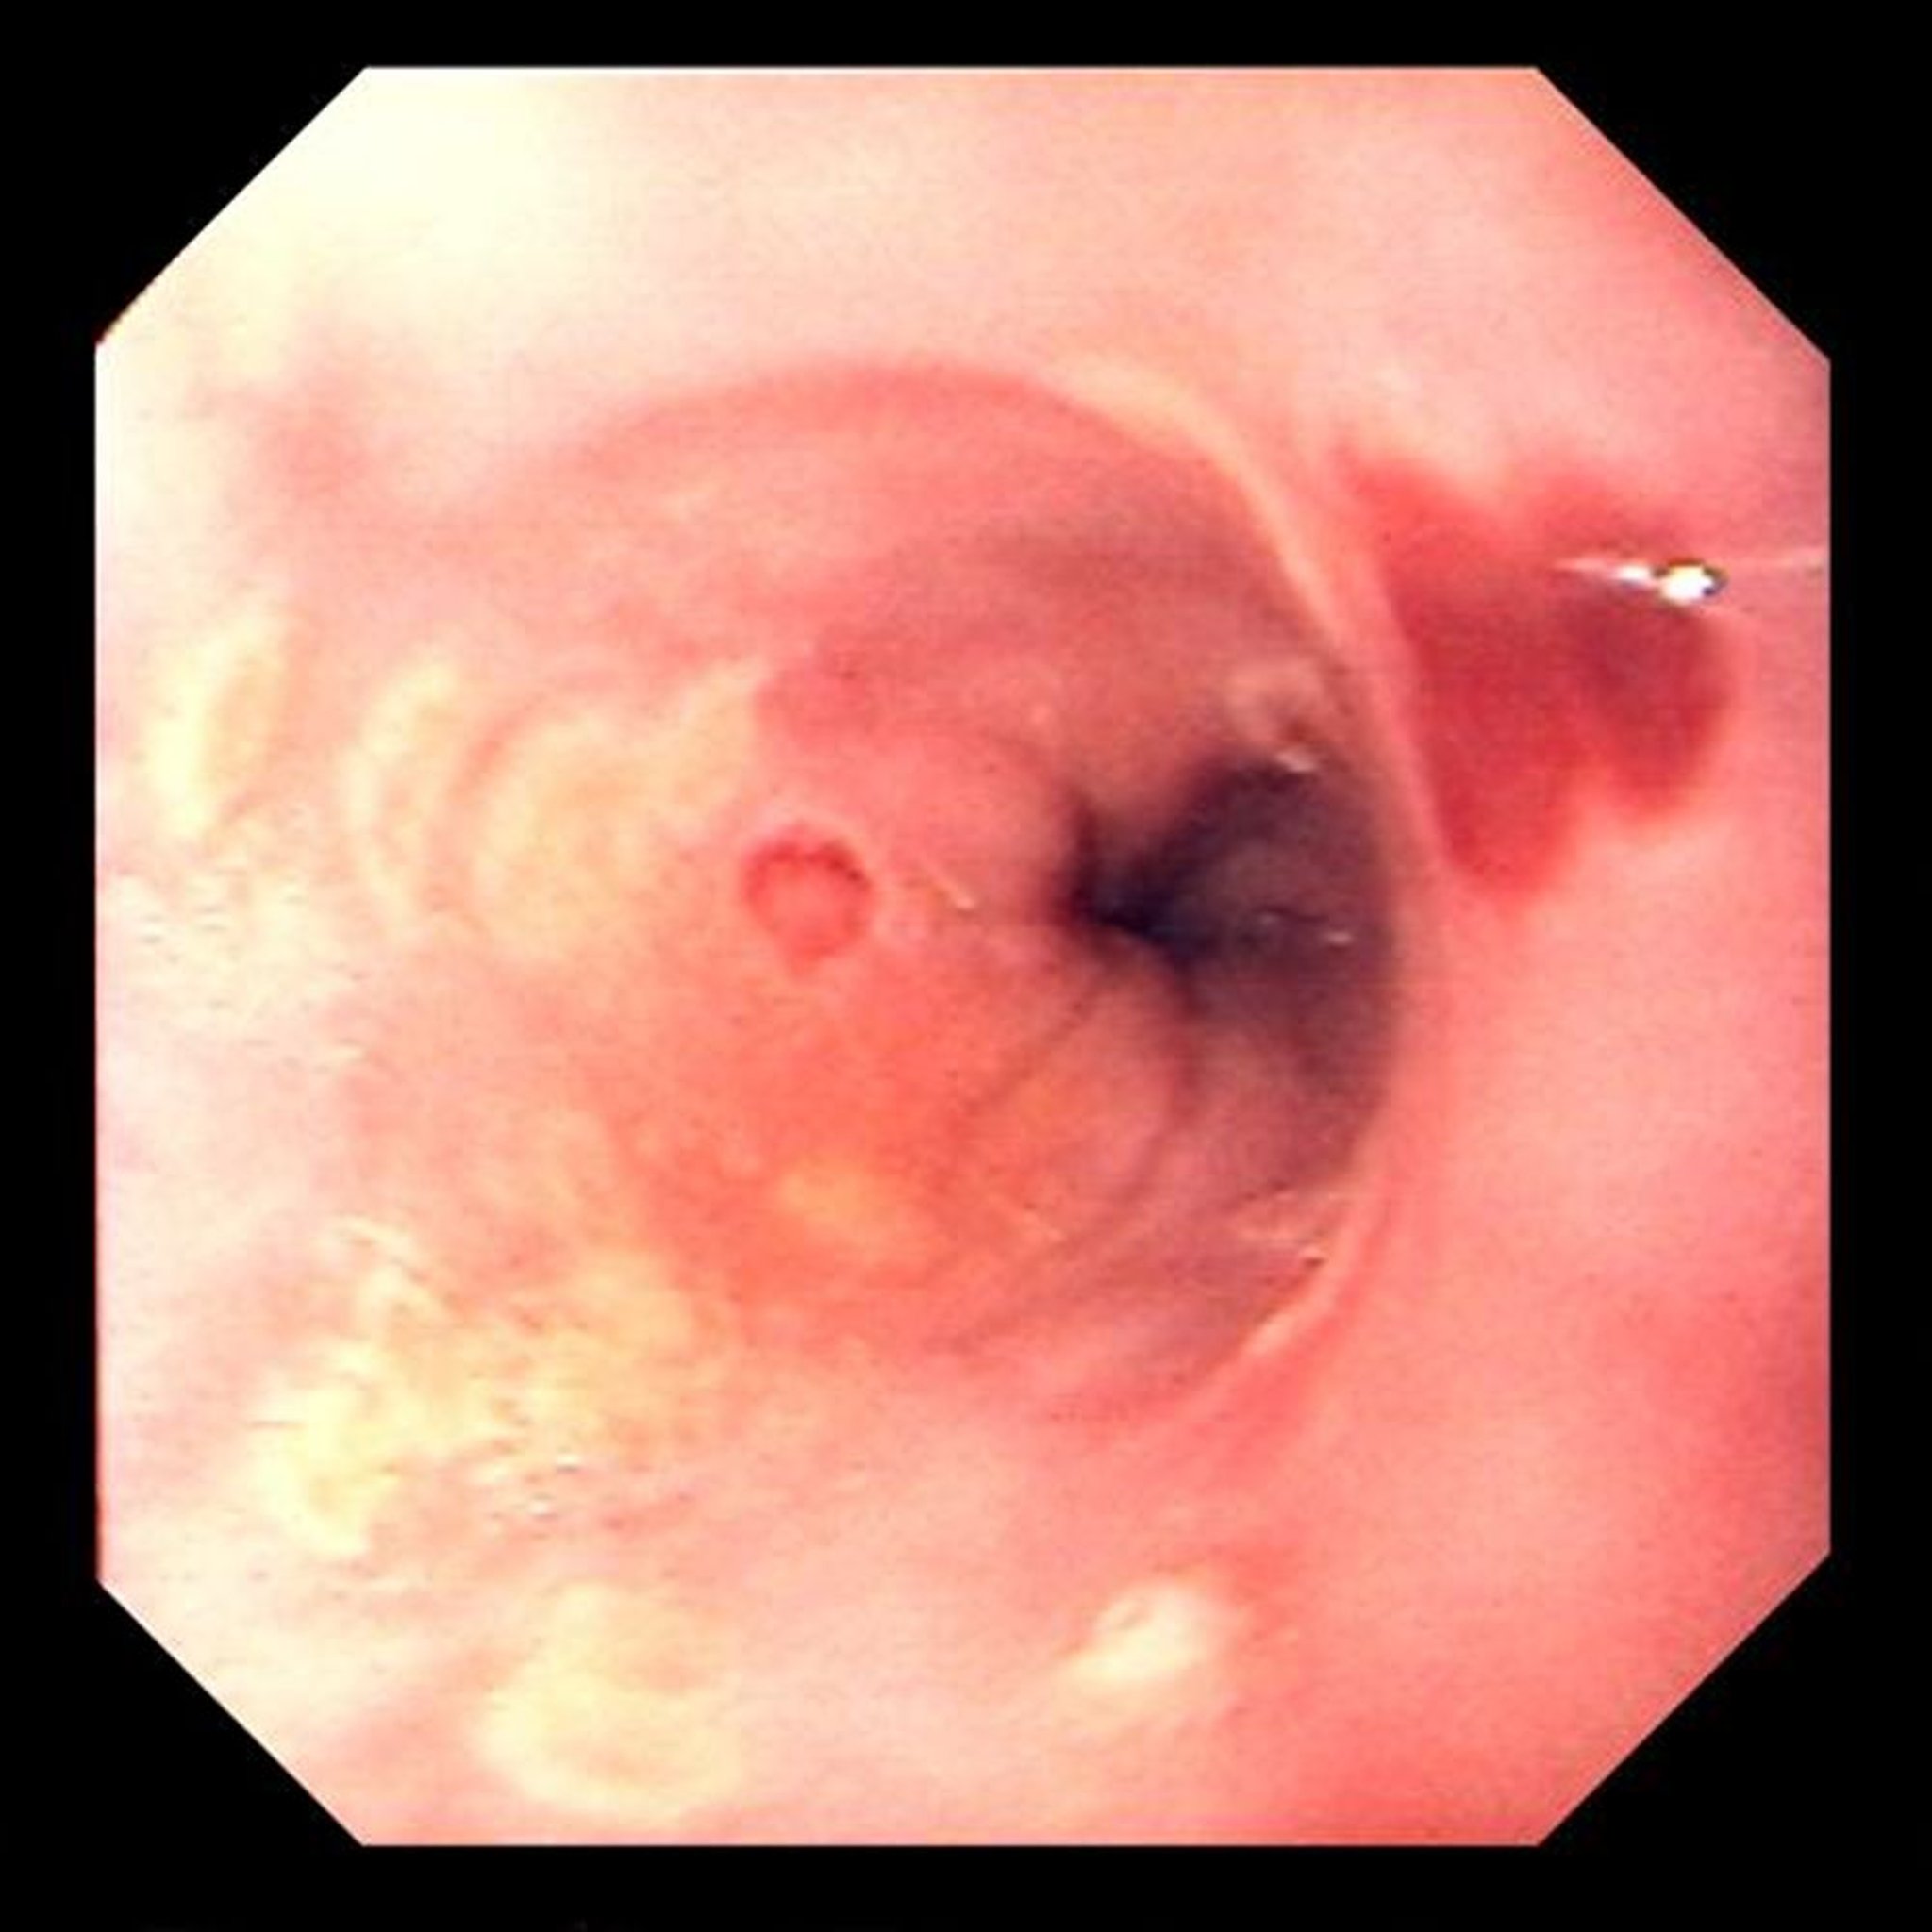

Œsophagite à herpès simplex

Les ulcérations focales sont typiques de l'œsophagite à virus herpes simplex.

Image provided by David M. Martin, MD.